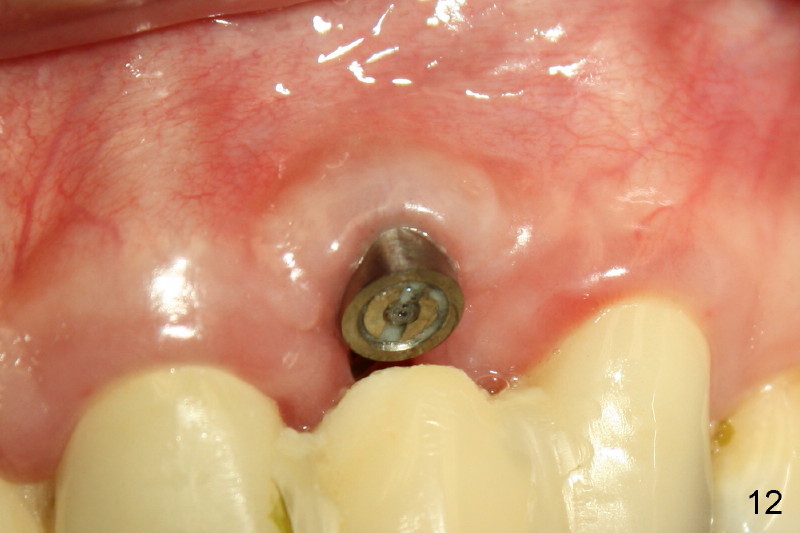

Segmental Osteotomy for Misplaced Implant

This corrective surgery was performed by Dr. Bernee Dunson.

Xin Wei, DDS, PhD, MS 1st edition 12/21/2011, last revision 12/23/2011